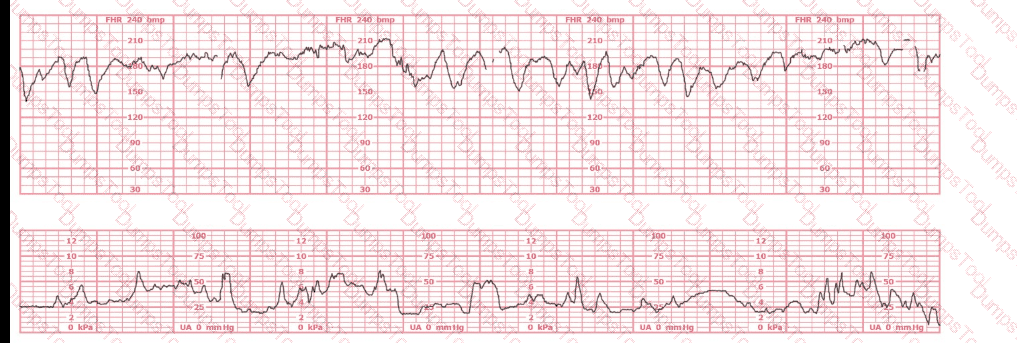

The black pattern represents the heart rate pattern for Baby A. The blue pattern represents the heart rate pattern for Baby B. A possible etiology of the baseline fetal heart rate of Baby A is:

A 30-year-old woman (G2P0) is experiencing preterm labor at 26-weeks gestation. She is receiving magnesium sulfate for neuroprotection. Her external fetal monitoring tracing over the past 30 minutes is shown. The next step would be to: